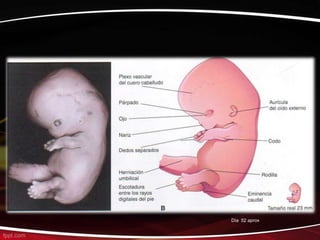

El documento describe las principales etapas del desarrollo embrionario humano desde el día 8 hasta la semana 8, incluyendo la formación del tubo neural, el corazón y los órganos internos, y el desarrollo progresivo del cuerpo y las extremidades.